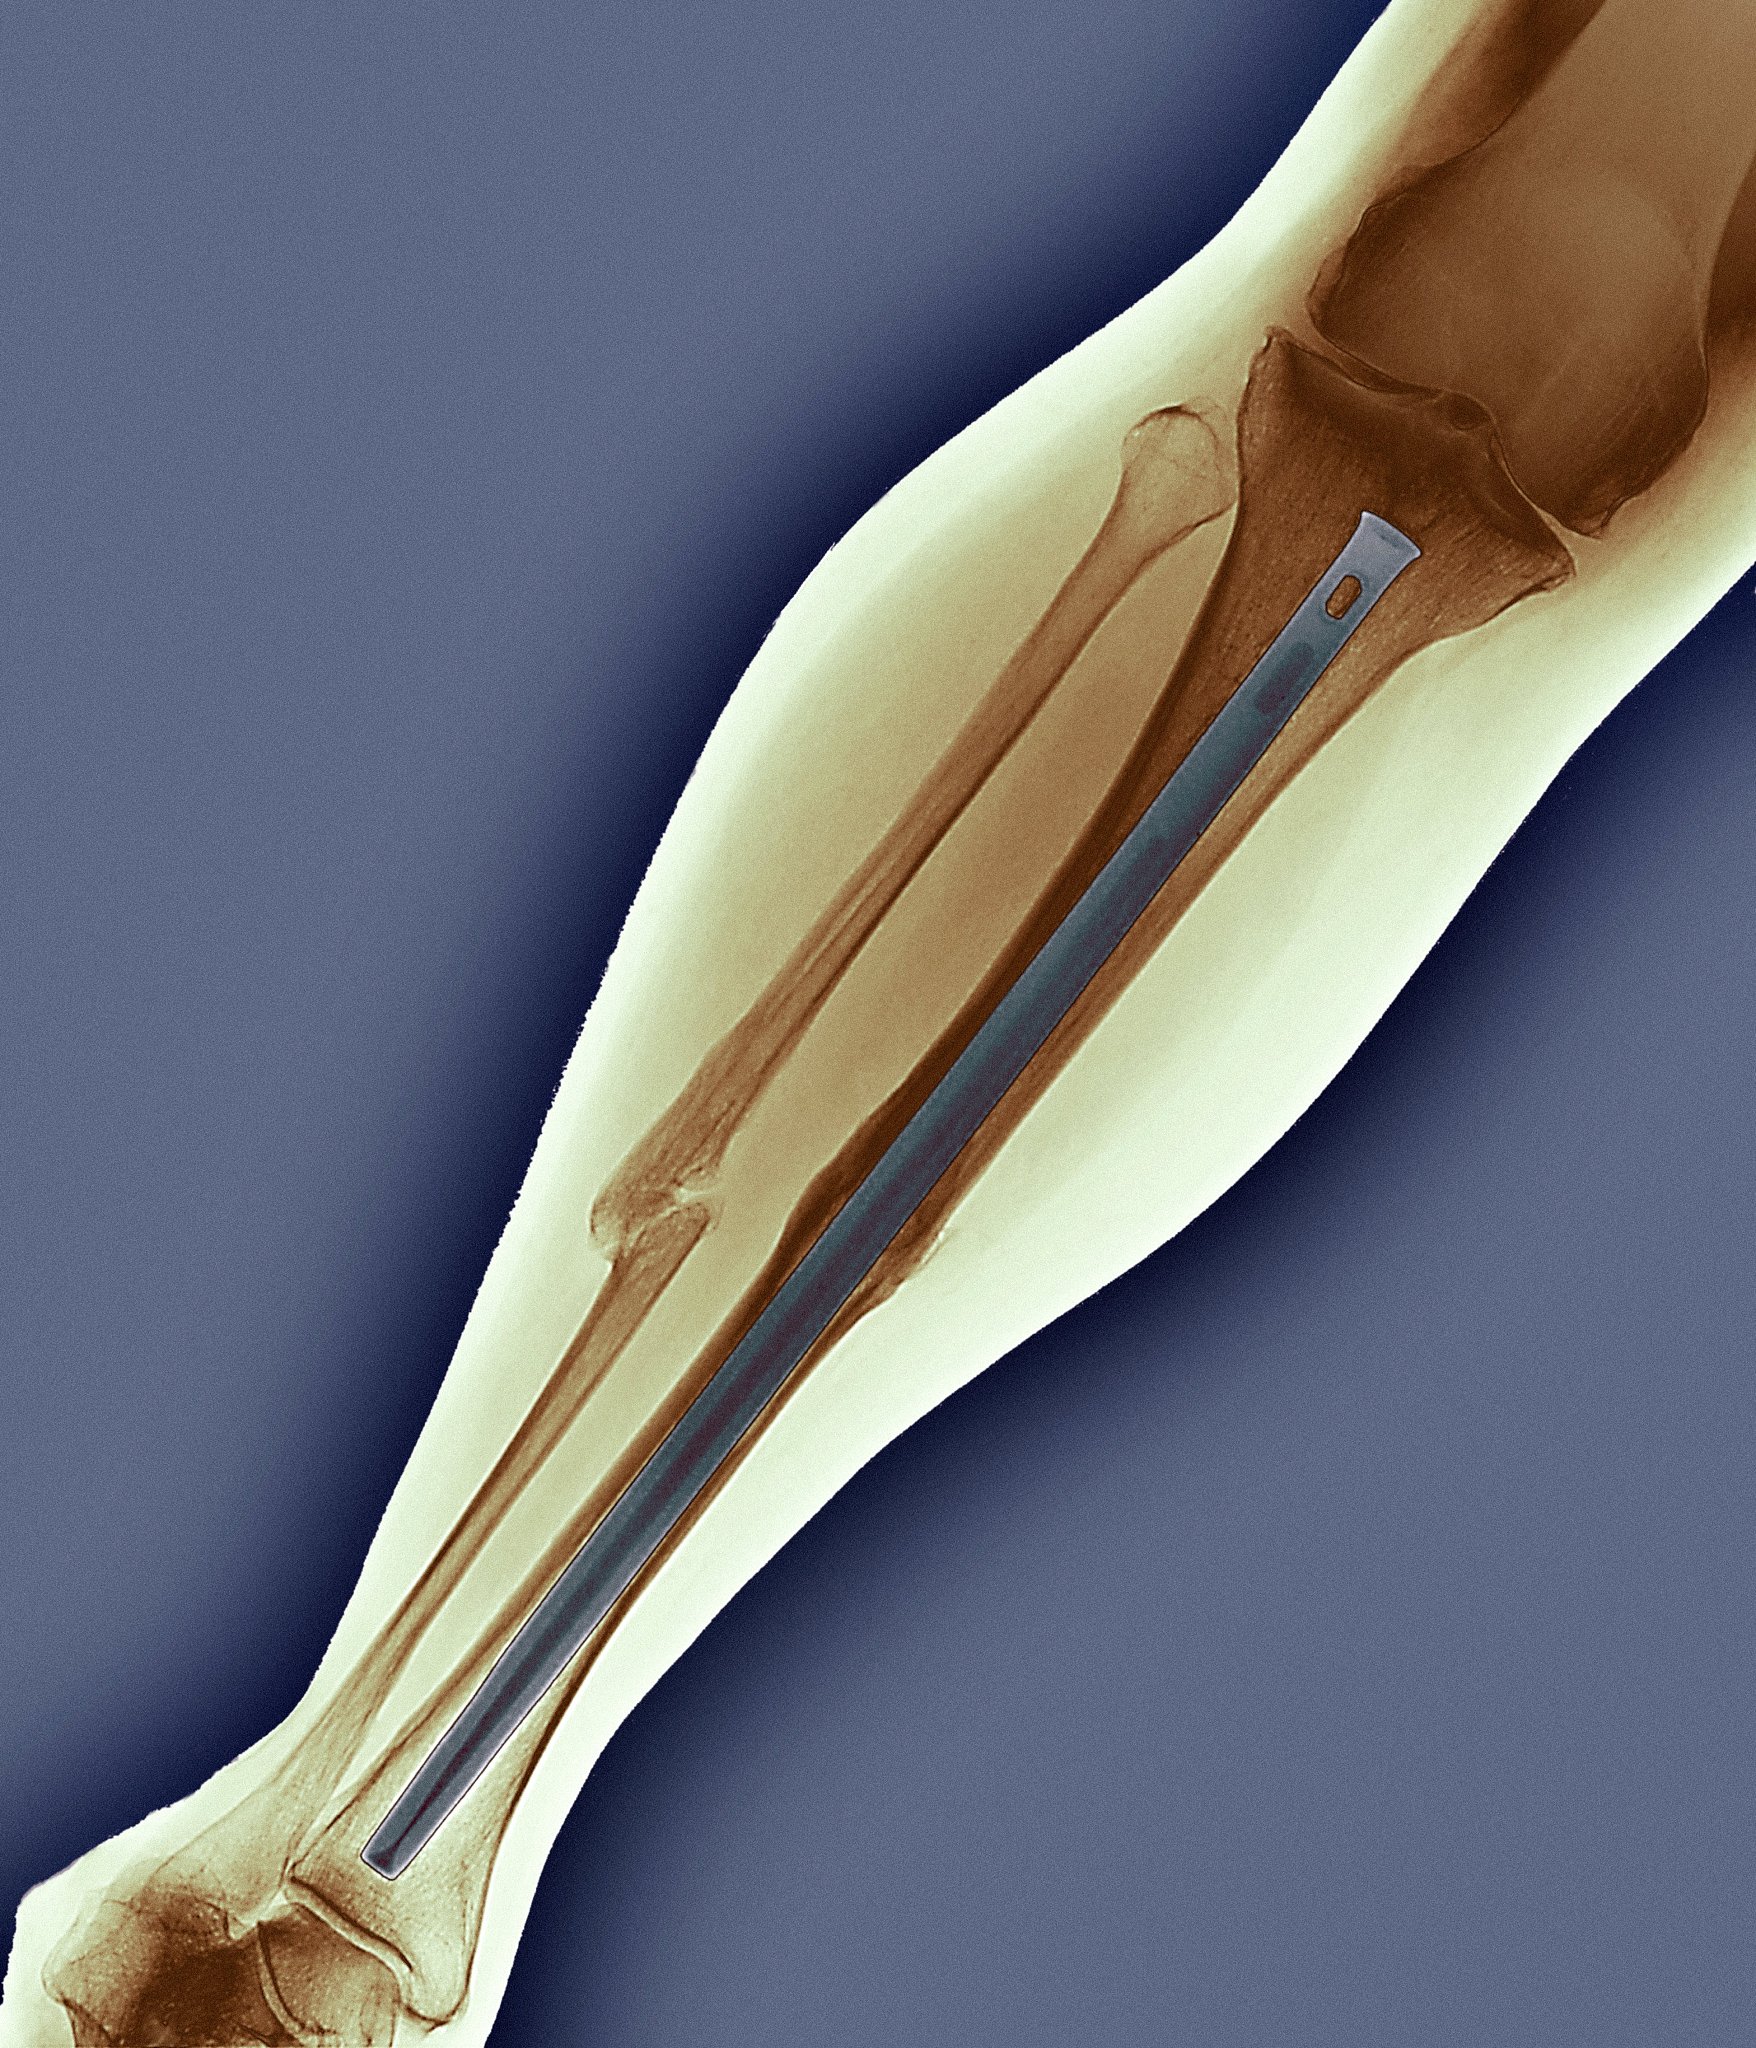

腓前韧带修复紧缩术是一种针对腓前韧带损伤的微创手术,旨在恢复踝关节稳定性,缓解疼痛,并改善关节功能。

腓前韧带修复紧缩术适用于:

• 腓前韧带损伤导致的踝关节不稳* 反复崴脚,保守治疗效果不佳* 运动爱好者,希望通过手术恢复运动能力